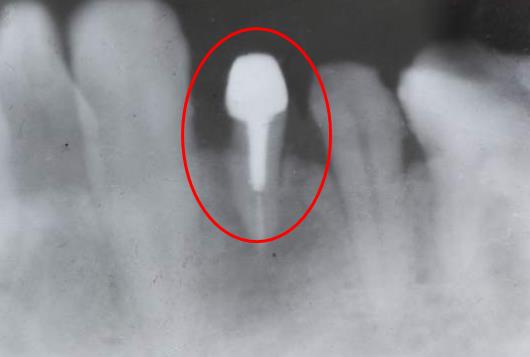

牙齒殘根打樁做冠後修複

治療後,發現牙根過短或者是固位力不夠,不能直接在上麵做牙冠的話,這時候就要考慮在根管治療幹淨後的牙根裏打入基樁,也就是加固的東(dong) 西,然後再充填完整,再做上麵的牙冠修複。